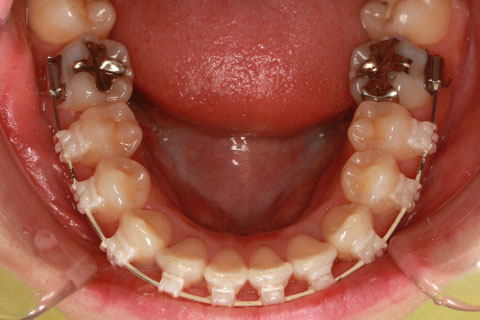

矯正期間24ヶ月

フルリンガル矯正1(上下の歯を舌側矯正で治療)

治療前

治療中

治療後

- 年齢・性別

- 33歳女性

- 治療期間

- 2年0ヶ月

- 抜歯

- 上顎4番抜歯。下顎5番欠損。

- 治療費

- 120万円(税込み)

- 備考

- フルリンガル矯正

- 治療内容

- 上顎前歯の叢生改善および下顎前歯の空隙閉鎖

- 施術の副作用(リスク)

- 装置が裏側について、目視ができないため、しっかりとブラッシングができているかどうかわかりにくい。